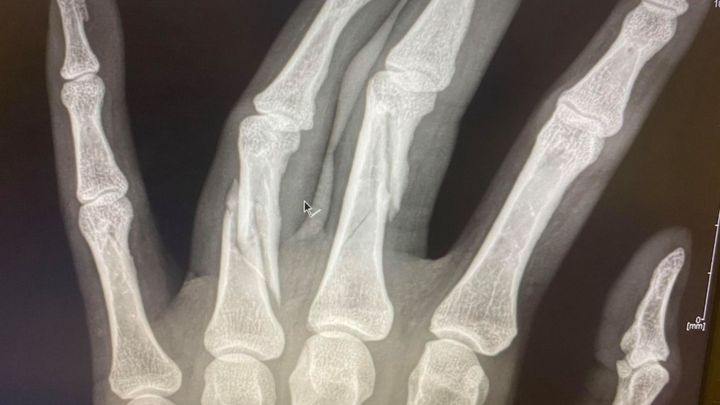

On October 7th, I was in a car crash with a semi-truck, causing multiple injuries, the most serious of which being 3 broken fingers. The injuries to my hand require surgery which will take place on October 19. Altogether, I will be in recovery from 3 - 4 months, while also recovering from an MCL tear.

Tuesday's surgery was a success. Once the surgeon began, he quickly realized the damage was more extensive than the x-rays showed. What was supposed to be a 2-hour surgery ended up taking over 6 hours. They had to reconstruct my middle and ring finger, with 11 screws and 2 pins in my pinky finger.